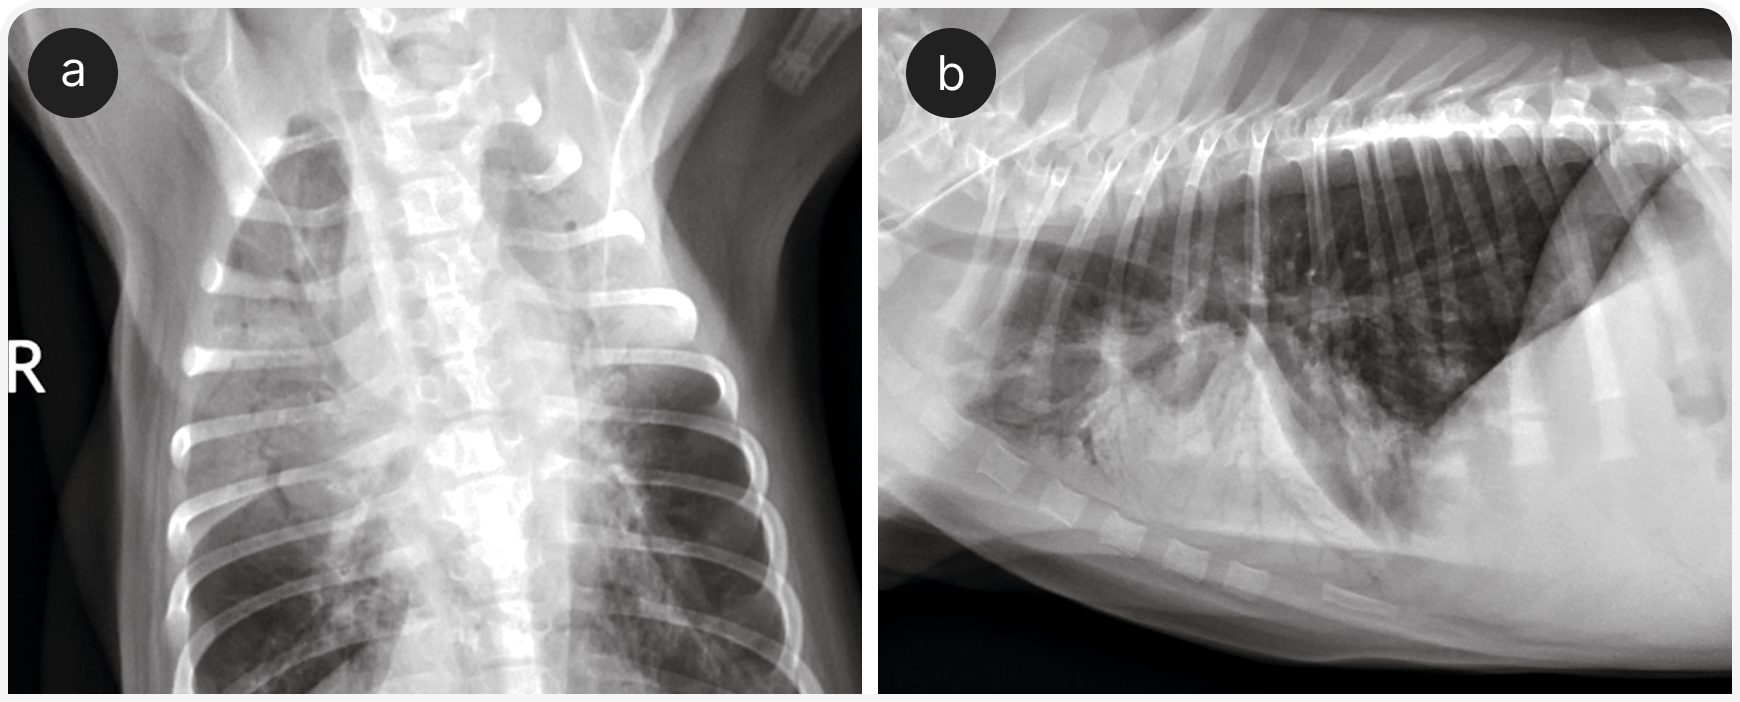

Для диагностики гемоторакса, транссудата в сравнении с экссудатом или септического выпота рекомендуется определить гематокрит, общее содержание растворенных веществ в плазме крови, содержание глюкозы, лактата, а также провести экспресс-цитологическое исследование выпота. После торакоцентеза показана рентгенография органов грудной клетки для выявления легочной буллы, объемного образования в легких, кардиомегалии или другой причины (Рисунки 6 и 7).

В этих случаях также возможно поражение легких и/или плевральной полости (например, ушибы легких или пневмоторакс), поэтому аускультативная картина изменчива; для выявления некоторых из этих изменений (например, плеврального выпота, отека легких или отсутствия признака скольжения) может быть полезен POCUS. Если проникающее поражение грудной стенки не очевидно сразу, для выявления его симптомов целесообразно провести рентгенографию органов грудной клетки, поскольку его требуется лечить хирургически (Рисунок 8).